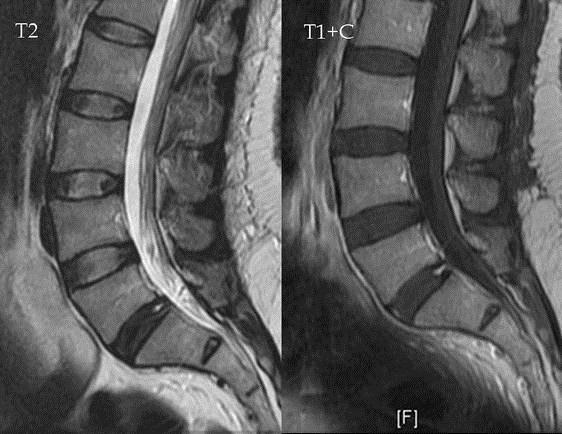

Самый информативный метод диагностики поясничного смещения дисков — МРТ. На полученных изображениях отчетливо визуализируются все поврежденные структуры: межпозвонковые диски, позвонки, мягкие ткани, спинномозговые корешки, кровеносные сосуды. С помощью МРТ можно установить локализацию выпячивания, оценить его форму и размеры. Также исследование позволяет выявить типичные признаки поясничного остеохондроза, спровоцировавшего формирование грыжи в этом отделе.

Беременность не является противопоказанием для проведения МРТ. Не отмечено случаев негативного воздействия магнитного поля на внутриутробное развитие плода. Но во время диагностической процедуры возможно повышение температуры околоплодных вод. Поэтому МРТ не проводится в 1 триместре, когда происходит закладка органов всех систем жизнедеятельности эмбриона.

На ранних сроках вынашивания ребенка этот метод диагностики используется только по жизненным показаниям. Обычно смещение дисков выявляется в ходе безопасного ультразвукового исследования с учетом результатов общеклинических анализов.

Выявить межпозвоночную грыжу удастся при помощи современных диагностических методов — магнитно-резонансной (МРТ) и компьютерной (КТ) томографии, а также КТ-миелографии. Благодаря этим исследованиям можно увидеть точное расположение грыжи или протрузии, ее величину, степень разрыва дискового кольца. Проводить эти обследования во время беременности запрещено.

Единственное исключение: в третьем триместре возможно провести МРТ в случае острых болей и защемления нервных корешков для выяснения дальнейших действий по ведению беременности и способам родоразрешения.